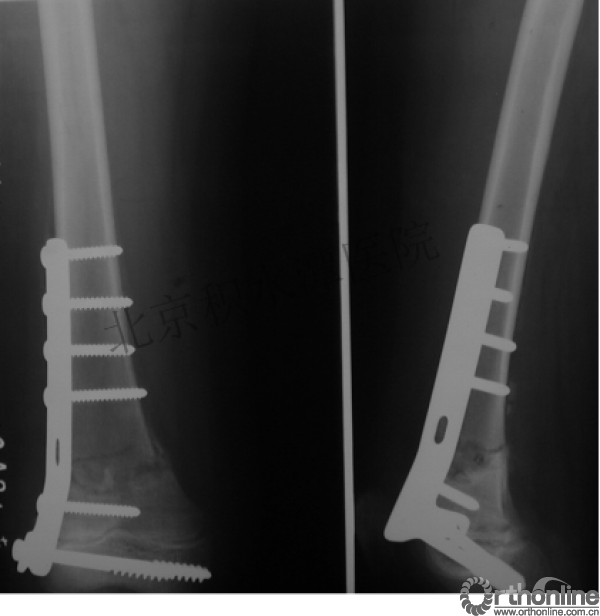

男孩、9岁,滑雪受伤,胫腓骨螺旋形骨折(粉碎性)

这个病例郭教授在积水潭医院骨科高研班时多次讲到,也在互动交流中惊人地看到,了解到现实之令人难以想象!

手法整复,石膏制动!

整复后7天

儿童具备强大的愈合潜力,同样也有极强的塑形能力